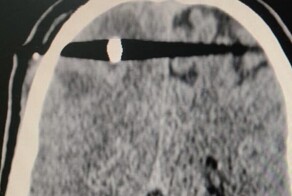

- Серпуховские врачи спасли мужчину с пулей в голове

- Россиянка 80 лет прожила с иголкой в головном мозге